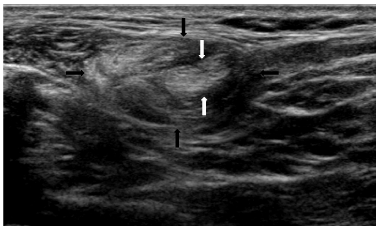

| Figure 1: Oblique US image of the left posterior cervical triangle showing a mass comprising a superficial, oval hyper-echogenic structure (black arrows) that contains multiple linear striations similar to the subcutaneous fat. This is suggestive of a lipomatous lesion. The deeper margin of the mass is inseparable from a hypo-echogenic linear structure (white arrows) containing linear striations, which is suggestive of muscle. The precise nature of the muscular component was unclear. A similar muscle was not present in the right side of neck. |